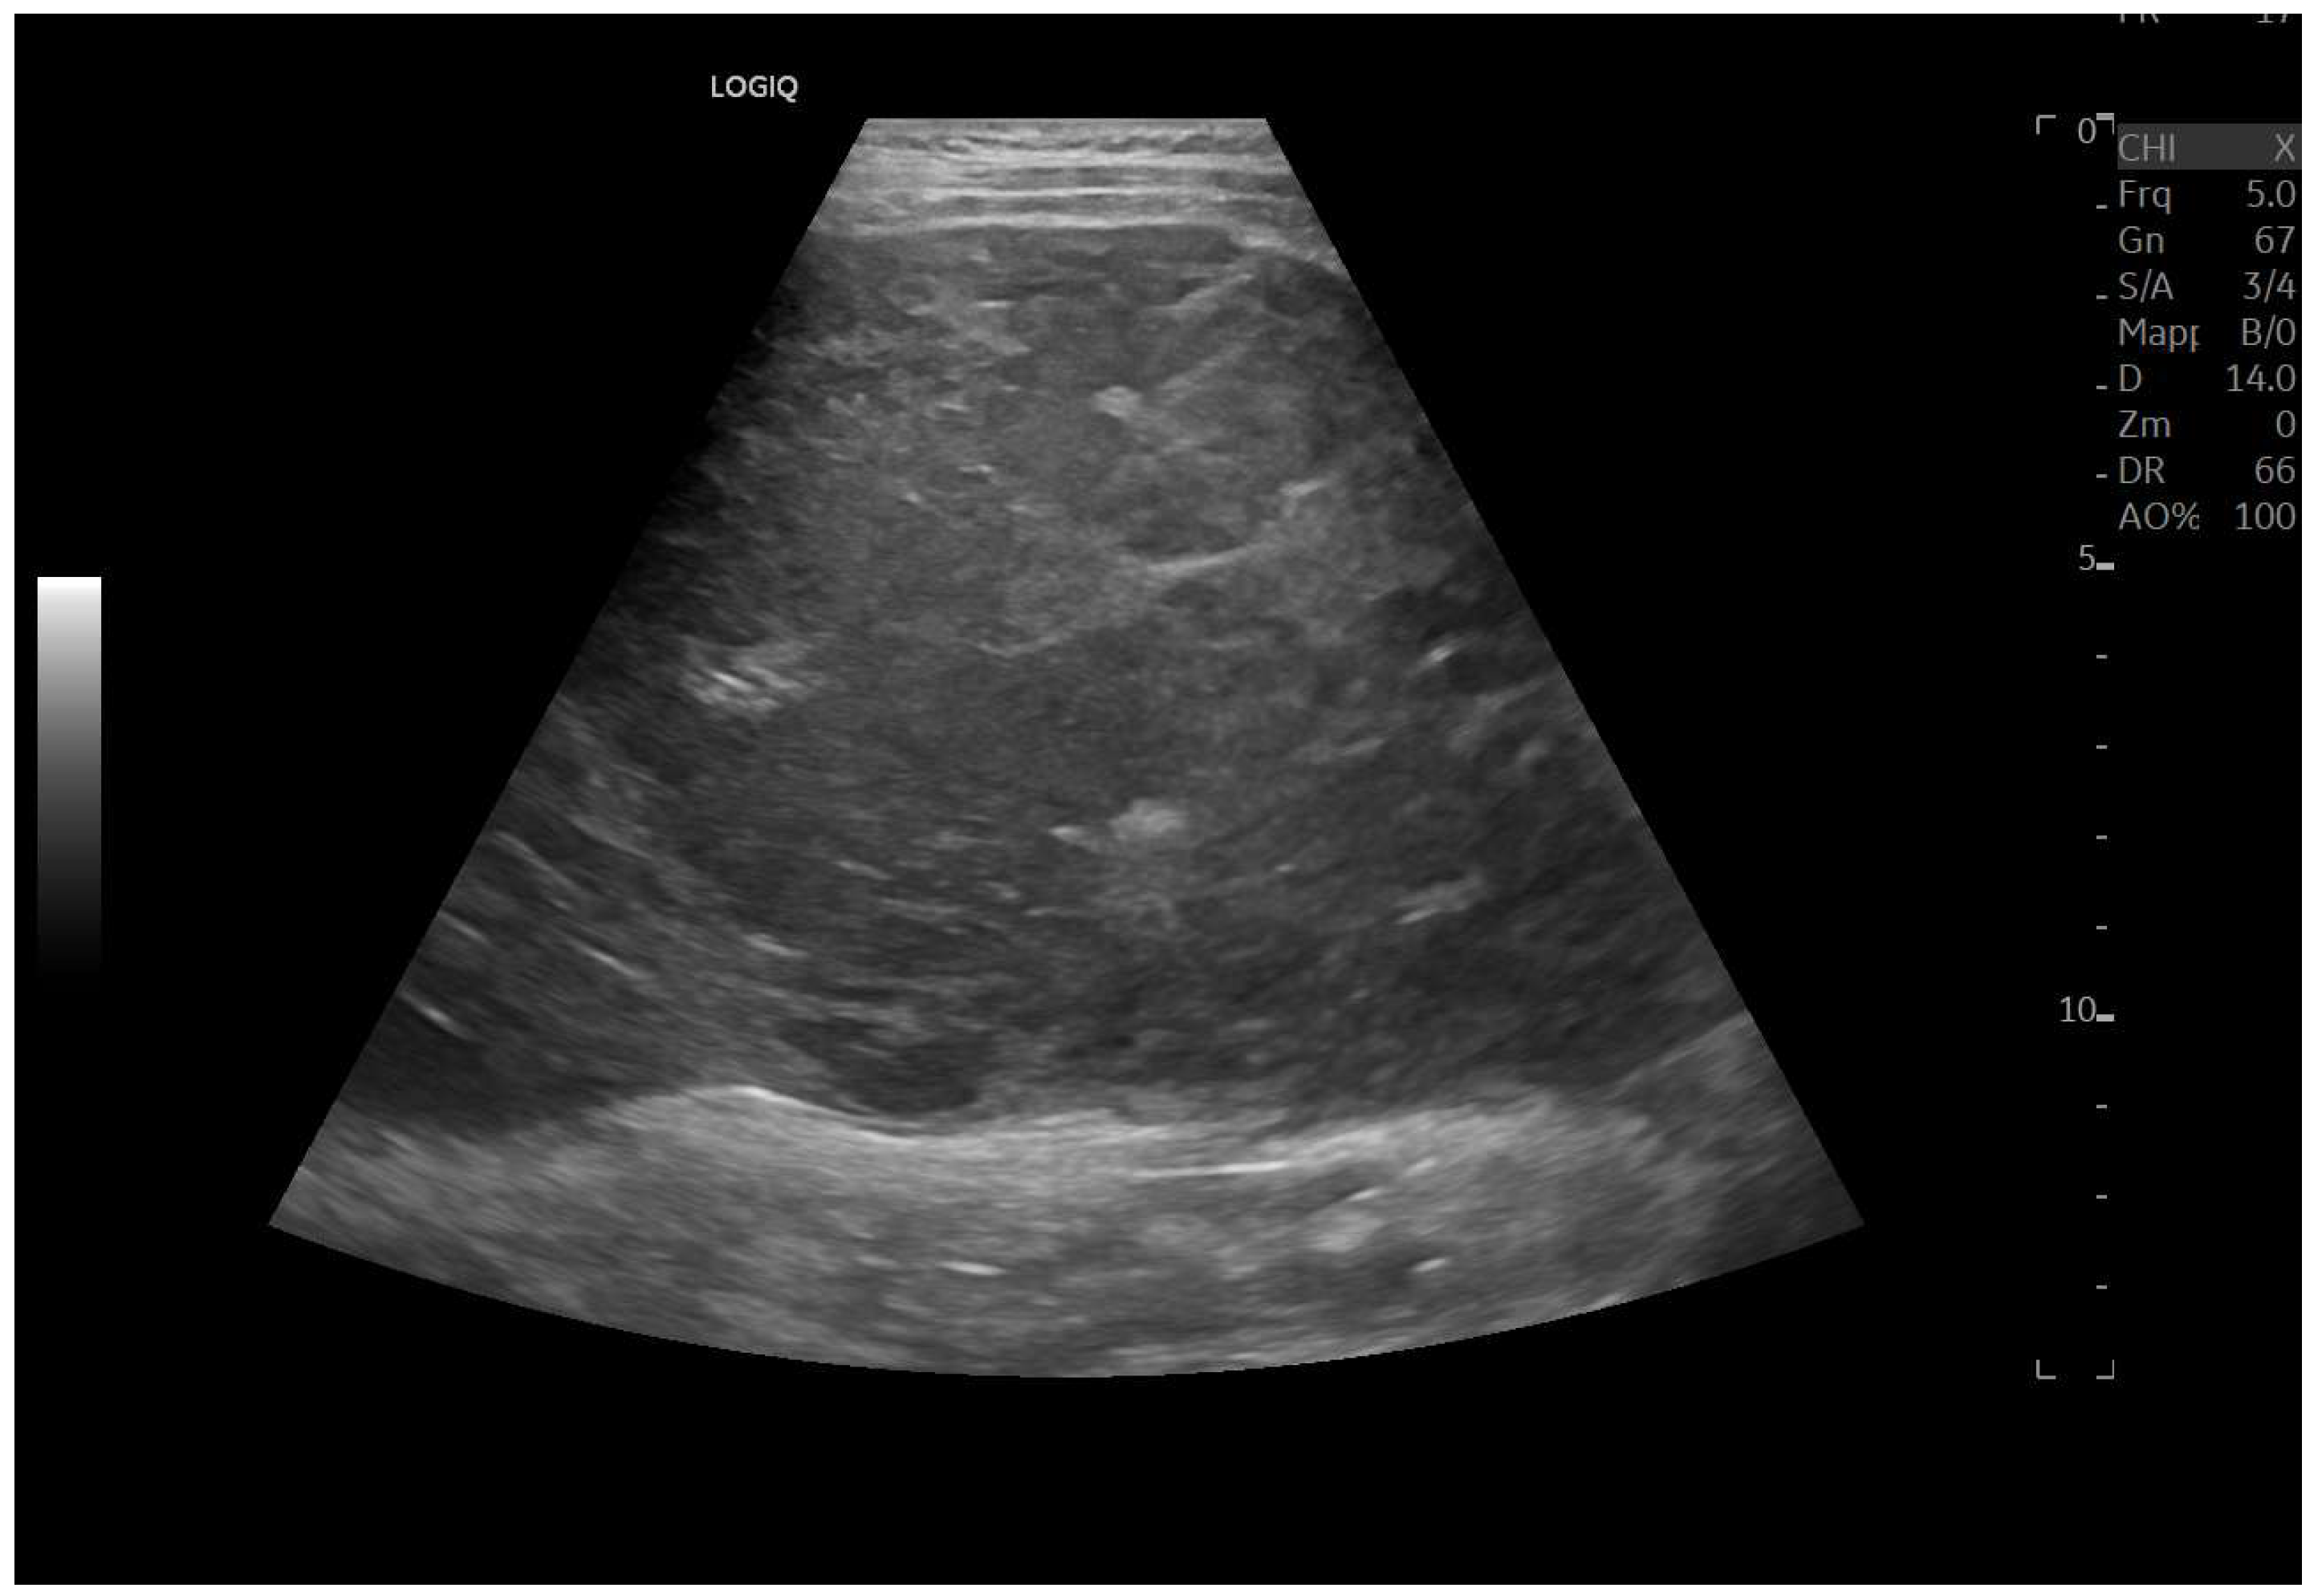

Ultrasound imaging is capable of identifying heterogeneous echotexture and hepatomegaly, which are early indicators of congestive hepatopathy [46]. Several studies have shown correlations between the extent of sonographic abnormalities and the severity of hepatic fibrosis or cirrhosis [36,47,48]. The most common ultrasound findings encompass a nodular hepatic surface, right-lobe volume reduction, smooth-to-rounded contour changes, and irregular outer profiles [49,50,51] (Figure 2). The echotexture appears granular and markedly heterogeneous, with hyperechogenic nodules of varying sizes [49,50,51] (Figure 3, Figure 4, Figure 5, Figure 6, Figure 7 and Figure 8).

Figure 2.

Detail with convex probe in oblique subcostal scan: note the rounded margins, the heterogeneous echotexture, particularly in the left segments, and a marked hypotrophy of the right lobe.